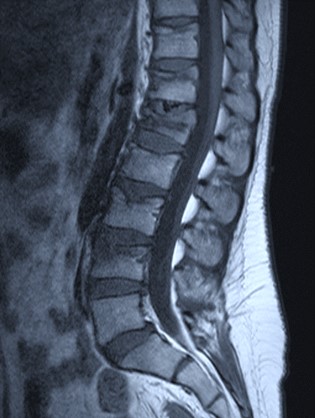

Vertbroplastika primenom stenta

View the embedded image gallery online at:

https://www.klinikaelit.com/minimalno-invazivne-porcedure#sigProId7e0694e114